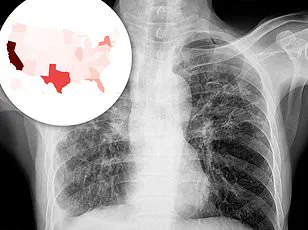

X-ray scans of the woman’s lungs revealed small nodules, a red flag for bacterial infection.

Further imaging and biopsies uncovered lesions in her liver, lymph nodes, pancreas, and brain—indications that the infection had spread far beyond the lungs.

Yet, the latest data from the Centers for Disease Control and Prevention (CDC) paints a stark picture: in 2024, the U.S. recorded 10,347 TB cases, marking an 8% increase from the previous year and the highest number since 2011.

In 80% of U.S. states, TB cases are now on the rise, a troubling signal that the disease is no longer a distant threat but a re-emerging challenge.

Medical scans revealed nodules in her lungs, an enlarged lymph node, and lesions in her liver, pancreas, and brain—evidence of a TB infection that had spread far beyond its usual confines.